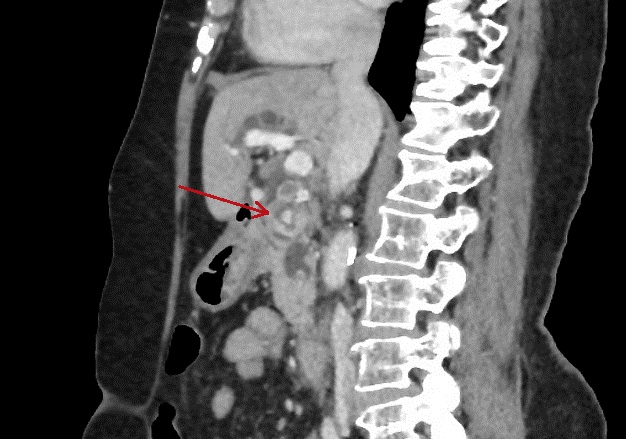

Calcul a la portion de bas du

canal choledoque ( fleche rouge ) . Meme cas en

coupe sagital , (image radiologique TDM + contrast

). |